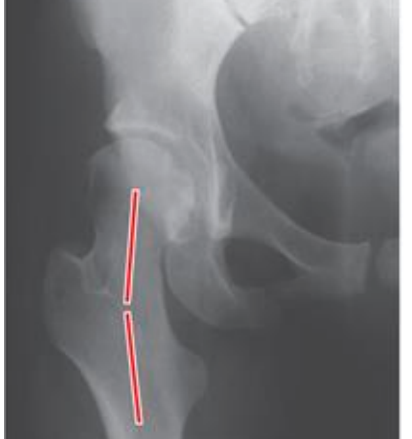

angle of inclination

-angle between the femoral neck and femoral shaft in the frontal plane

-adult normal ~125 degrees

-decreased angle = coxa vara <125

-increased angle = coxa valga >125 degrees